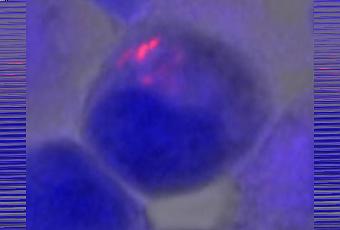

MENj facteur de virulence et cible thérapeutique en puissance : Les chercheurs de l’Université Colorado ont donc comparé les gènes dans la tuberculose avec ceux qui sont connus pour modifier les navettes d’électrons pour d’autres organismes. Ils ont finalement identifié un gène clé, nommé MENj. Ce gène produit une forme spécifique de molécule, MK (ménaquinone), spéc à la tuberculose. Les scientifiques montrent qu’une souche mutante de M. tuberculosis privée de ce gène MENj est alors privée de sa capacité à infecter les cellules macrophages humains. Ainsi, alors que » normalement » Mycobacterium tuberculosis, (en rouge sur visuel du haut) se propage dans les cellules macrophages (à gauche), privée de son gène MENJ est éteint, la bactérie est stoppée dans sa course (voir visuel du bas).